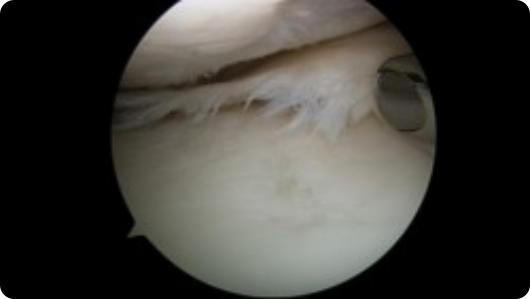

Arthroscopic image of an ACL tear Arthroscopic image of an ACL reconstruction

ACL Reconstruction